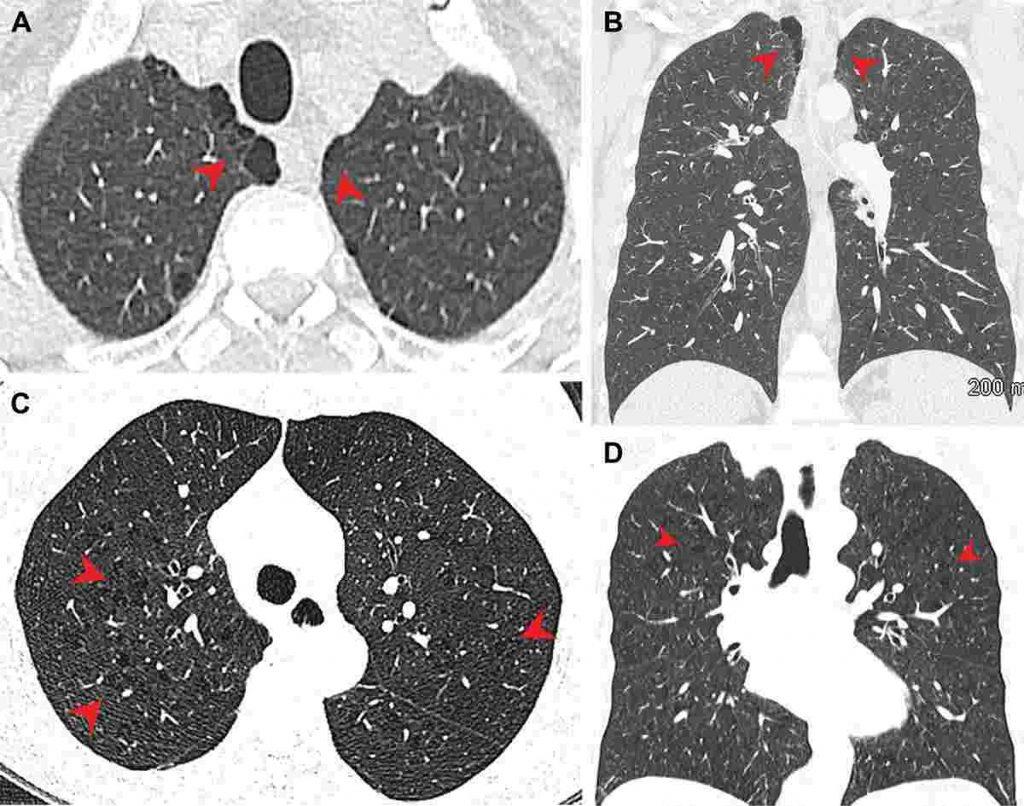

Vedci prišli k záveru, že fajčiari marihuany majú vyššiu mieru emfyzému (pozn. redakcie: ide o trvalé, abnormálne rozšírenie dýchacích ciest spojené s poškodením pľúcneho tkaniva) a ochorení dýchacích ciest v porovnaní s fajčiarmi tabaku.

Výskumníci k tomu záveru došli potom, ako urobili vyšetrenie hrudníka 56 fajčiarov marihuany, 57 nefajčiarov a 33 fajčiarov, ktorí fajčili iba tabak v rokoch 2005 až 2020. Zistili vyššiu mieru paraseptálneho emfyzému a zápalových zmien dýchacích ciest u fajčiarov marihuany.